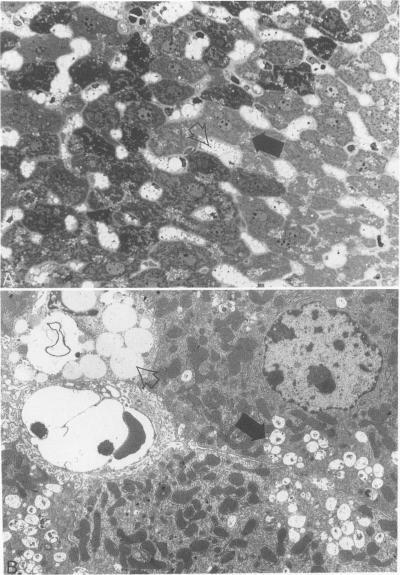

This report describes the clinical and pathologic alterations found in mice that have a recessively inherited, essentially complete deficiency of the lysosomal enzyme beta-glucuronidase. Affected animals have a shortened life span and are dysmorphic and dwarfed. Abnormal gait and decreased joint mobility correlate with glycosaminoglycan accumulation in articular tissue and cartilaginous and bony lesions result in extensive skeletal deformation. In these enzyme-deficient animals, lysosomes, distended by fine fibrillar and granular storage material, are particularly prominent in the macrophage system but also occur in other tissues including the skeletal and central nervous systems. The clinical and pathologic abnormalities in these mutant mice closely parallel those identified in humans with mucopolysaccharidoses (MPS). Therefore, these mice provide a well-defined genetic system for the analysis of the pathophysiology of mucopolysaccharidosis type VII, which has many features in common with the other MPS. The mutant mice provide an attractive animal model to test potential therapies for lysosomal storage disease.

本报告描述了在具有隐性遗传、溶酶体酶β-葡萄糖醛酸酶基本完全缺乏的小鼠中发现的临床和病理改变。患病动物寿命缩短,身体畸形且矮小。异常步态和关节活动度降低与关节组织中糖胺聚糖的积累相关,软骨和骨病变导致广泛的骨骼变形。在这些酶缺乏的动物中,被细纤维状和颗粒状储存物质扩张的溶酶体在巨噬细胞系统中尤为突出,但也出现在包括骨骼和中枢神经系统在内的其他组织中。这些突变小鼠的临床和病理异常与黏多糖贮积症(MPS)患者中发现的异常非常相似。因此,这些小鼠为分析VII型黏多糖贮积症的病理生理学提供了一个明确的遗传系统,该疾病与其他MPS有许多共同特征。这些突变小鼠为测试溶酶体贮积病的潜在治疗方法提供了一个有吸引力的动物模型。